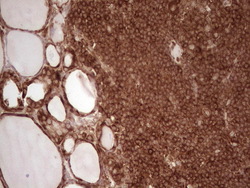

- Main image

- Experimental details

- Immunohistochemical staining of paraffin-embedded Human tonsil within the normal limits using anti-WIBG mouse monoclonal antibody. (Heat-induced epitope retrieval by 1 mM EDTA in 10mM Tris, pH8.5, 120C for 3min, TA806496)

- Validation comment